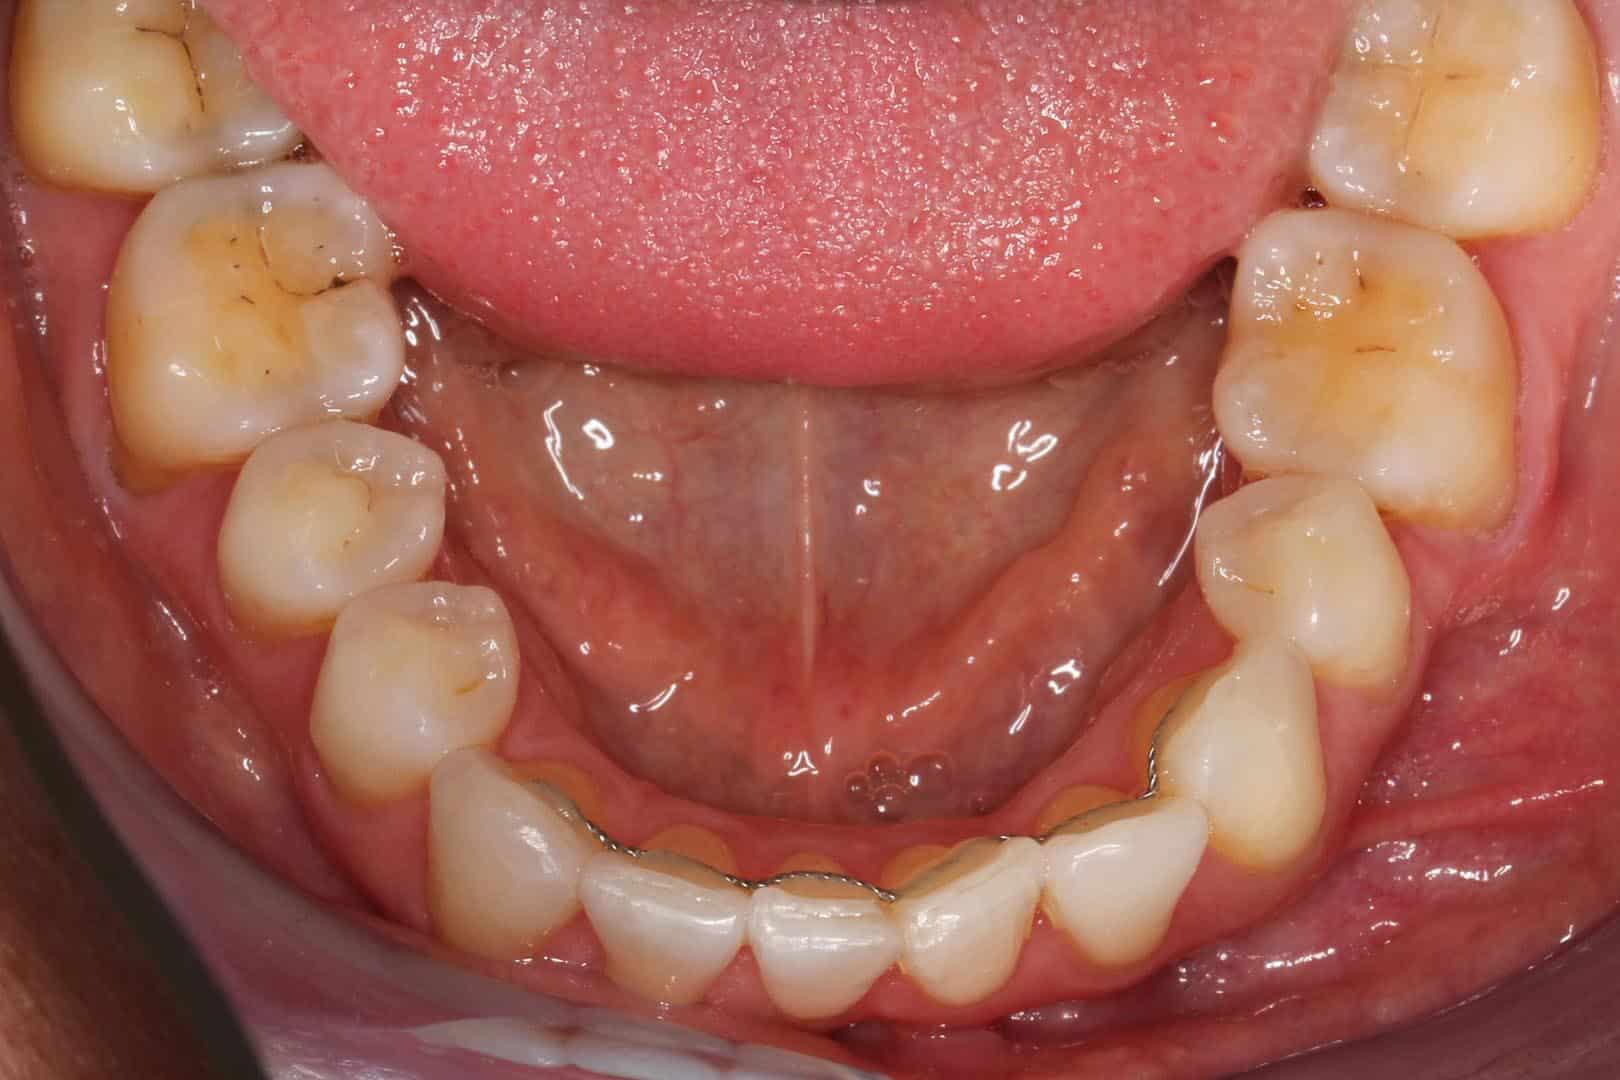

Dette er den samme metoden som benyttes til å låse tennenes posisjon etter reguleringsbehandling. Behandlingen krever to tannlegebesøk, og involverer å tilpasse en metalltråd langs tannbuen, før den festes bak tennene, fra hjørnetann til hjørnetann. Det første besøket fokuserer på å ta et avtrykk, slik at tannteknikeren skal kunne forme bøylen, og det andre besøket er for å feste bøylen til tennene. Metallbøylen er stabil, holdbar og diskret, men vil kunne være synlig fra innsiden. For de som finner avtrykkstagningen noe ubehagelig, kan digitalt avtrykk være et alternativ, selv om det generelt er noe mindre presist.

Før- og etterbilder